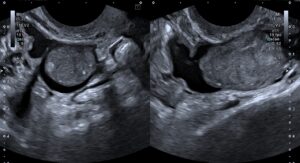

Patient presented for follow-up 4 months later. The collection in the endometrial cavity had resolved and endometrium measured 5 mm. The left adnexal ultrasound findings were as follows –

Figure 4: The hydrosalpinx appeared unchanged in size; however, the soft tissue component had increased in size, appeared lobulated and measured 6 x 2.2 cm.

Figure 5 – Video: The left adnexal lesion. Vascularity was noted in the soft tissue component on Doppler.

The interval change in the morphology of the left adnexal lesion was highly suspicious for malignant neoplasm of the fallopian tube, and thus a strong possibility of the same was raised.